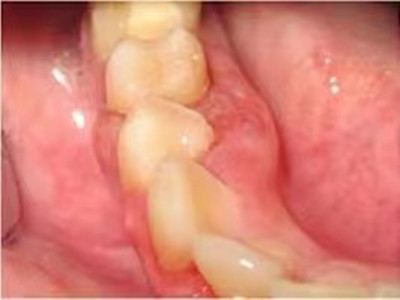

牙龈癌在口腔癌中仅次于舌癌而居第2位,组织学类型绝大多数为分化程度较高的鳞状细胞癌。牙龈癌好发于前磨牙区及磨牙区,下牙龈癌较上牙龈癌为多见,上下之比为2:1。牙龈癌发病年龄多为40-60岁,男性多于女性。

牙龈癌多源于牙间乳头及龈缘区,溃疡呈表浅、淡红,以后可出现增生。由于黏骨膜与牙槽突附着甚紧,较易早期侵犯牙槽突骨膜及骨质,进而出现牙松动,并可发生脱落。X线片可出现恶性肿瘤的破坏特征虫蚀状不规则吸收。